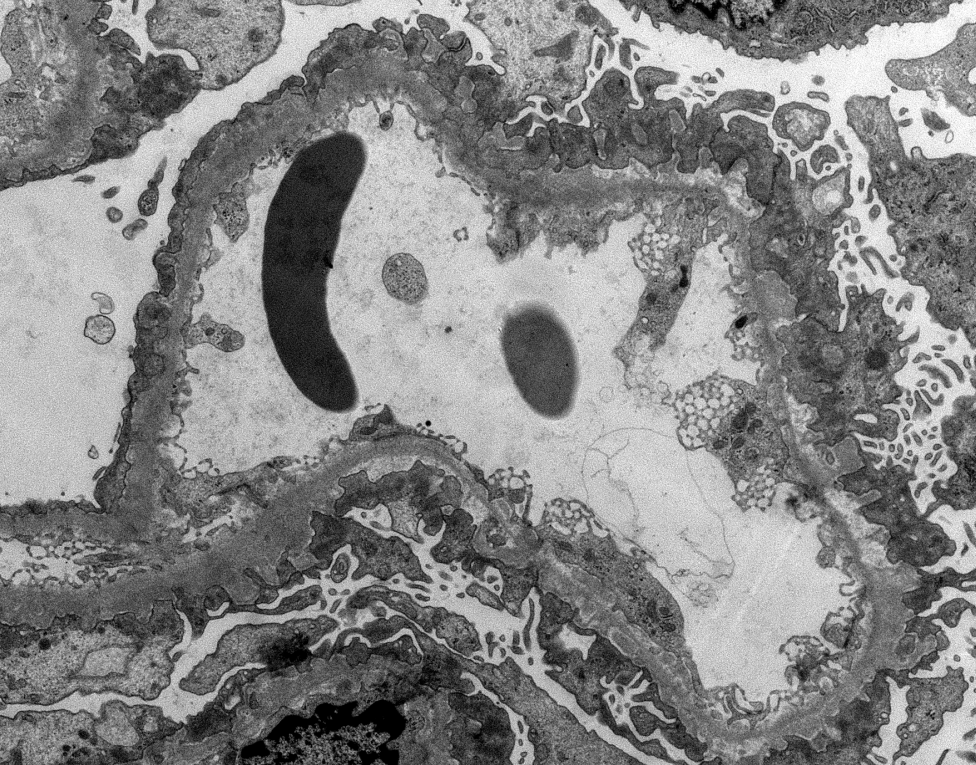

Illustrative example of a segmental membranous nephropathy pattern (segmental granular IgG staining) which is often seen with NELL-1+ (IHC) MN as in this case. Deposits present in only some loops by EM. #renalpath #pathtwitter #nephrology

NELL-1 IHC can also be tricky to interpret as there is significant podocyte cytoplasmic staining in the negative control. Must show granular capillary wall deposits which match deposits by IF and EM. #renalpath #pathwtitter #nephrology